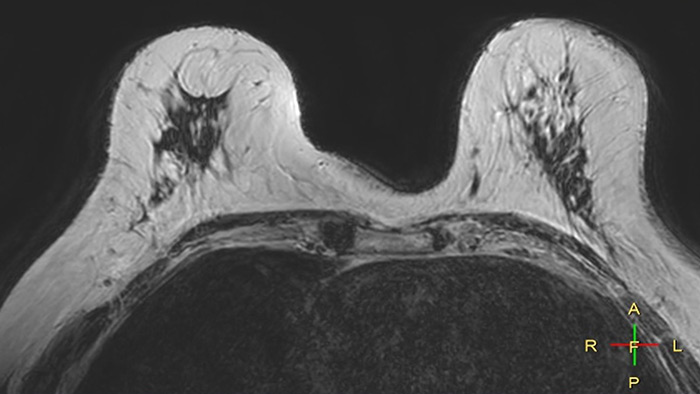

Compressed SENSE, scan time 3:54 min Voxels acq 0.8 x 0.72 x 1.8 mm Voxels recon 0.63 x 0.63 x 0.9 mm

C-SENSE factor 12

SENSE, scan time 6:32 min Voxels acq 0.8 x 0.8 x 1.8 mm Voxels recon 0.63 x 0.63 x 0.9 mm

SENSE factor 3

The time gain with Compressed SENSE was also used to increase resolution in order to help radiologists identify the tumor characteristics more confidently which may be used for a more personalized treatment. For example, in breast imaging, resolution is crucial for visualization of very small lesions. Compressed SENSE allows to scan thinner slices, allowing a 3D isotropic sequence which can provide increased diagnostic confidence for the radiologists.